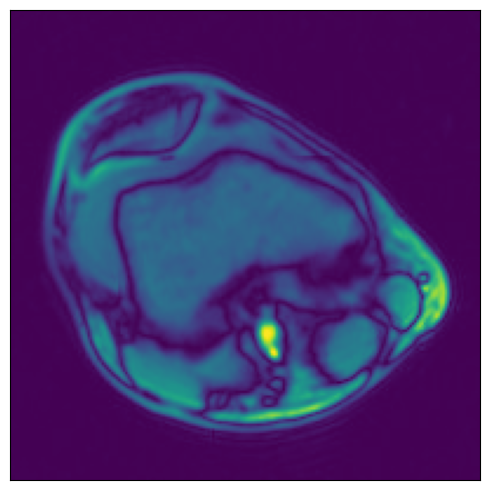

Higher dimensionality#

NumPy reader can also be used to load data of higher dimensionality (up to 6 dimensions). Let’s demonstrate with our 3D MRI arrays.

[8]:

print(f"Sample shape: {tensor_3d.shape}")

plot_tensors(

Sample shape: (5, 512, 512)

../../../../_images/examples_general_data_loading_numpy_reader_dynamic_mode_16_1.png

Region-of-interest (ROI) API#

In the example shown above, we see that the relevant data is concentrated in the upper left quadrant of the image and the rest does not contain useful information. This is not true for all the images in the dataset, but it will serve us as a good example to demonstrate ROI reading.